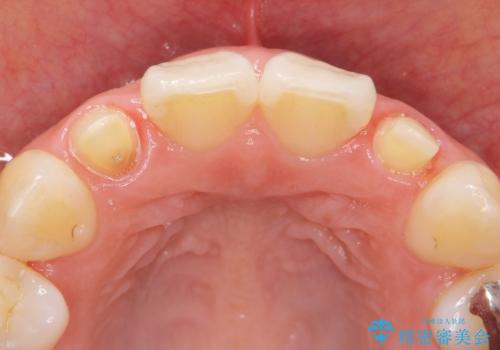

矯正治療後、矮小歯をセラミッククラウンにより理想的な歯の大きさに仕上げました。

- ¥280,000 (仮歯×2本、クラウン×2本)費用は治療当時の料金となります

クラウンの種類:オールセラミッククラウン スペシャル